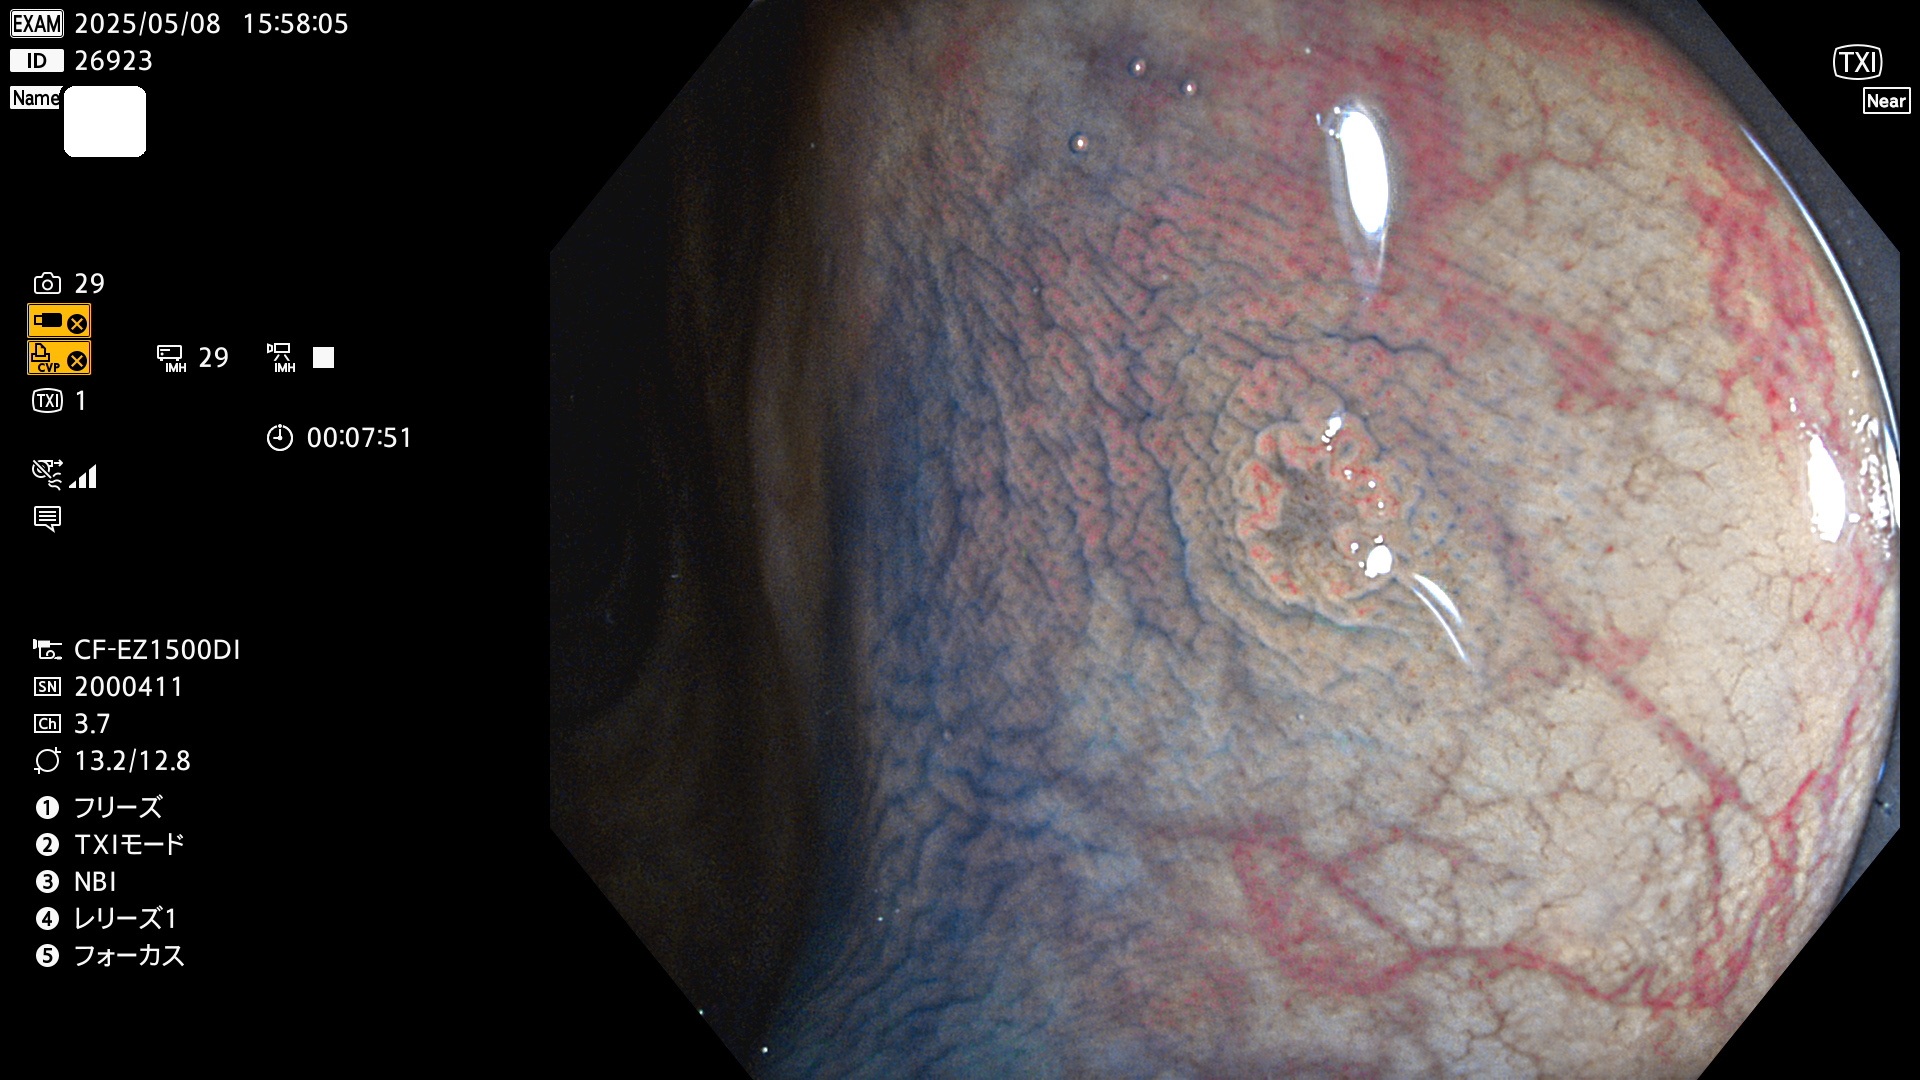

完全に平坦な物をUb、陥凹している物をUcと呼びます。Ubは認識が困難で、Ucはびらん(炎症)と紛らわしいために見落とされやすく、「内視鏡後・大腸癌」の原因になります。

専門的)何故、陥凹していると危険? 癌遺伝子の変異が蓄積すると細胞分裂が盛んになり隆起するのでは?と通常は思われるでしょう。しかし実際は逆です。これは2022年の記事にある「細胞はストレスに直面したら細胞分裂を止める(細胞老化に入り休眠する)という生命の基本的現象」によるものです(Oncogene Stress)。細胞老化を起こすのが癌抑制遺伝子で、この安全装置(ブレーキ)が壊れると癌になります(休眠からの覚醒)。ですから陥凹は「まだ癌では無いが癌化の直前」を意味します。特に「小サイズなのに陥凹している」病変は短期間に腫瘍進化(IntraTumor Heterogenity⇒2021年記事)が起きたことを意味します(=ゲノム不安定性

抽出の対象期間 2025年5月8日〜5月11日の4日間(48件の検査)14個 (14/48=29%)